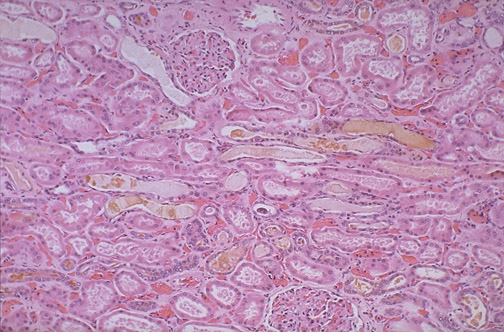

This section of renal cortex reveals tubules containing hyaline casts that are bile stained in a patient with hyperbilirubinemia.